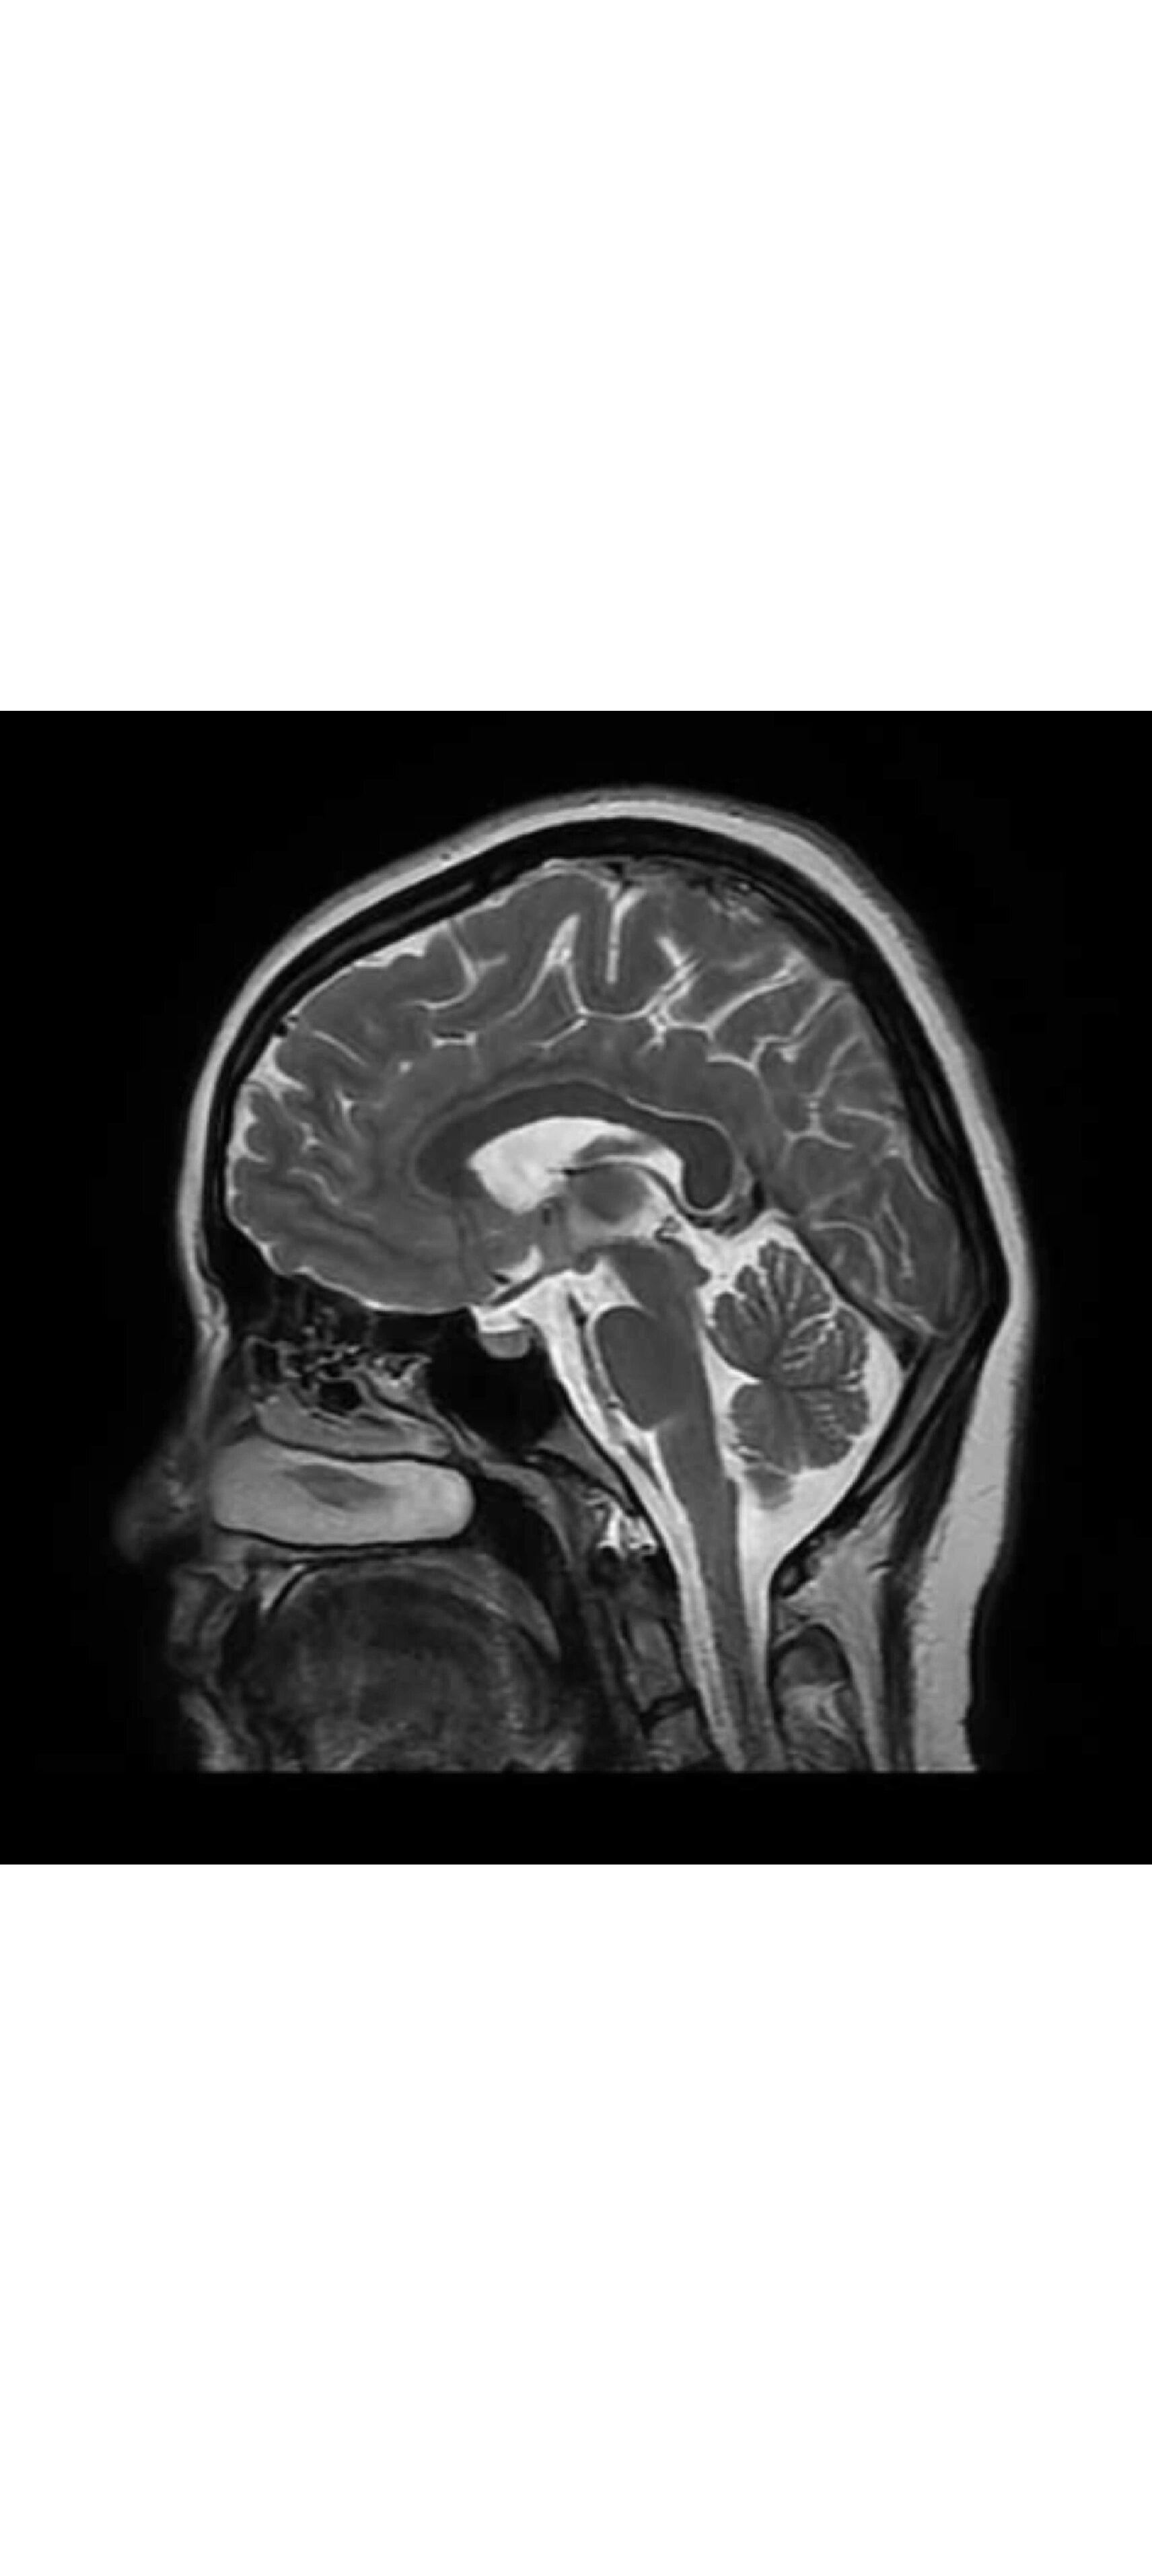

mri脑部影像

这可能是全网最高清的离体人脑mri扫描图像/医学资料